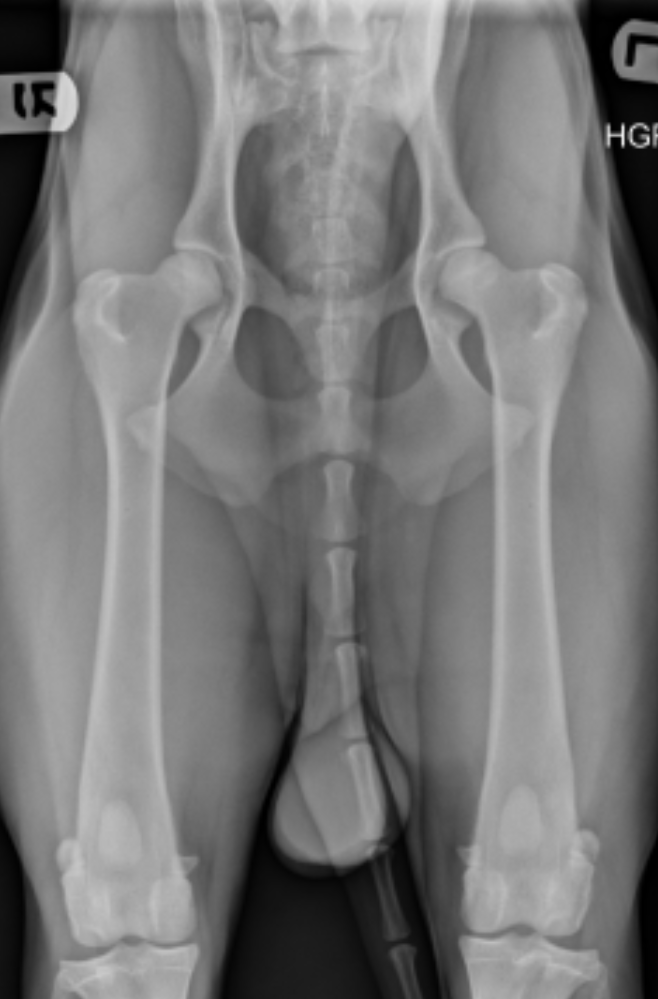

The PennHIP method accurately assesses, measures, and interprets hip joint laxity. Contrary to the singular, subjectively scored, conventional hip-extended radiographic view used by hip screening systems globally, the PennHIP method consists of three separate radiographs — the distraction view, the compression view, and the hip-extended view — and is shown to be a more accurate and better predictor for the onset of OA.

The distraction view and compression view are used to obtain accurate and precise measurements of joint laxity and congruity, respectively. The hip-extended view, sometimes called the OFA view, is used to obtain supplementary information regarding the existence of OA of the hip joint.

The radiographs pictured here are of the same dog, yet the hip joint laxities in each view look very different. Notice that the hips in the distraction view with the hips positioned in a neutral weight-bearing orientation appear to be much looser than they do in the hip-extended view.

The obvious contrast in joint laxity between the distraction and hip-extended views demonstrates the fundamental difference between the two radiographs. The looser the joint on the distraction view, the greater is the chance that the hip will develop OA. The hip-extended view tends to mask true hip joint laxity because the joint capsule is wound up into a tightened orientation when the hips are extended. This explains why measurable joint laxity on the distraction view is always greater than the measurable laxity from the hip-extended view. In fact, distraction laxity can be up to 11 times greater, depending on the breed of dog under study.